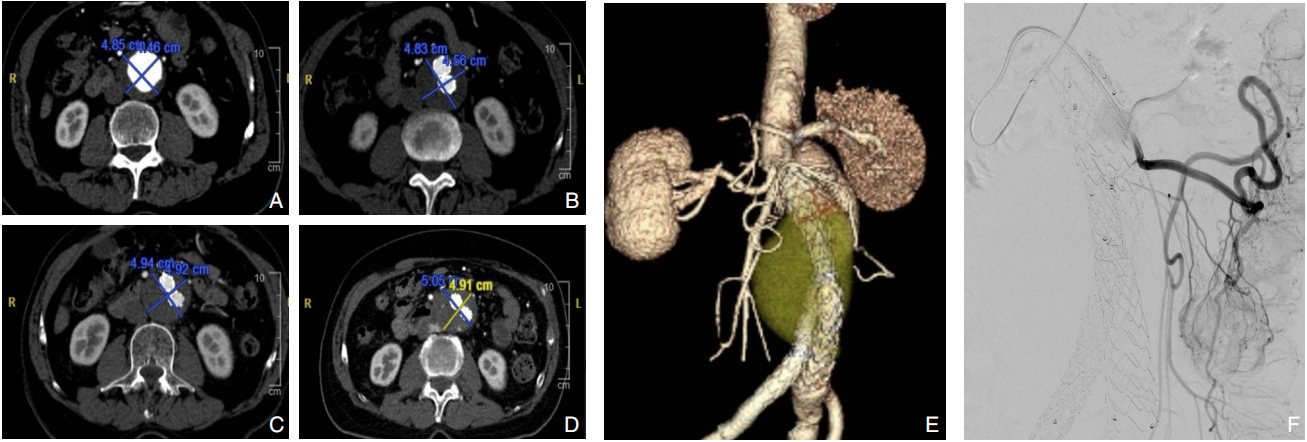

- 腹主动脉瘤腔内修复术中纤维蛋白粘合剂瘤腔填充技术专家共识